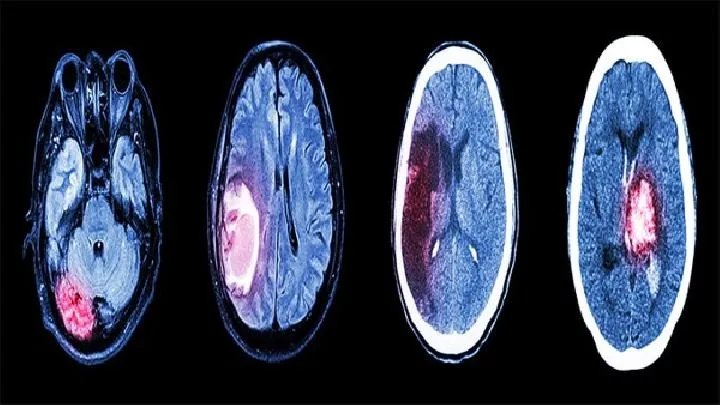

5、脑细胞介入疗法:对治疗部位进行一系列的生物物理刺激和生物化学效应,改善脑细胞的代谢环境,增加代谢酶活性,使受损的脑细胞代谢加快,增加损伤细胞的可复性,干扰和抑制异常脑电,脑磁的发生和传播,促进脑功能的恢复。